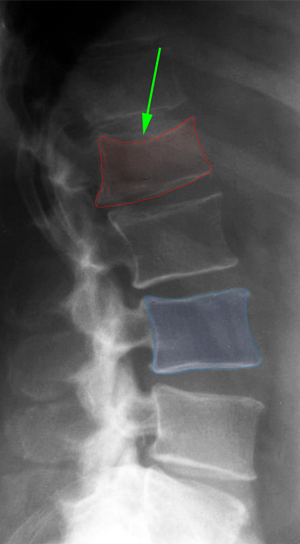

Οπίσθια θωρακοοσφυϊκή σπονδυλοδεσία με βίδες και ράβδους, και πεταλεκτομή, σε ασθενή με ασταθές κάταγμα Ο1 σπονδύλου. |